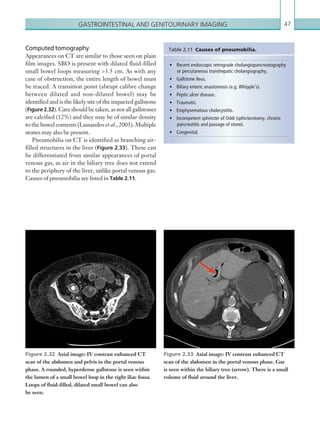

PRIMARY ASSESSMENT

CT HEAD:Vault #/base of skull #/orbital#/facial bones#

Subdural bleed/extradural bleed

Other:

Patient name

Hospital ID

Date

Reporting radiologist

CT CHEST: Pneumothorax/haemothorax/pneumomediastinum/thoracic aorta injury

Rib #...........................................................................Thoracic spine #..................................................................................